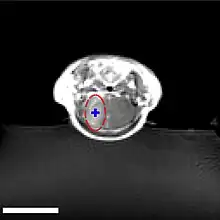

Les ultrasons peuvent être focalisés sur n'importe quel domaine du cerveau. C'est ainsi que l'on peut ouvrir la barrière hémato-encéphalique sélectivement sur des régions délimitées du cerveau. Les médicaments administrés pénétreront alors sur la zone ainsi ciblée[138]. On peut suivre le ciblage des zones par une IRM simultanée : il suffit d'administrer un produit de contraste IRM, comme du gadolinium convenablement chélaté, qui pénètre dans le cerveau à travers les parties de la barrière hémato-encéphalique ouvertes. Ces parties deviennent alors visibles en IRM. Les produits de contraste ne sont pas en mesure de franchir la barrière aux endroits où elle n'est pas ouverte.

Sur le modèle animal de la souris, on a utilisé des ultrasons focalisés dans le domaine de 0,5 à 2 MHz[139], avec de brèves impulsions de l'ordre de la milliseconde, répétées à intervalles de 1 s, pour une durée totale inférieure à une minute[140]. La fréquence optimale se situe au-dessous de 1 MHz[141]. La puissance acoustique instantanée est inférieure au watt, et donc la puissance moyenne de l'ordre du mW. Les microbulles utilisées sont en général des microbulles autorisées pour l'échocardiographie de contraste. Elles ont typiquement un diamètre de 3 à 5,5 μm, et sont composées typiquement d'albumine humaine, remplie d'octafluoropropane ou de gaz lourd semblable[142].